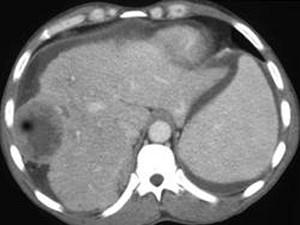

问题 女,47岁,曾患乙肝,现右上腹及肝区疼痛、腹胀,消瘦乏力半月,AFP阳性,CT扫描如图,请选择最可能答案 ( )

选项 A、肝转移瘤 B、肝包虫病 C、肝血管瘤 D、肝脓肿 E、肝癌

答案 E